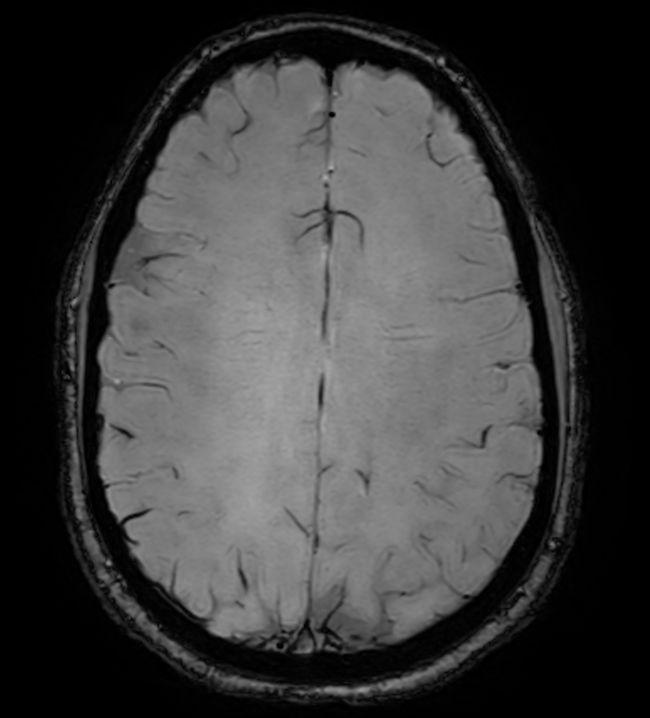

3D VIEW - T1w TSE (axial reformat)

Pre-Gado